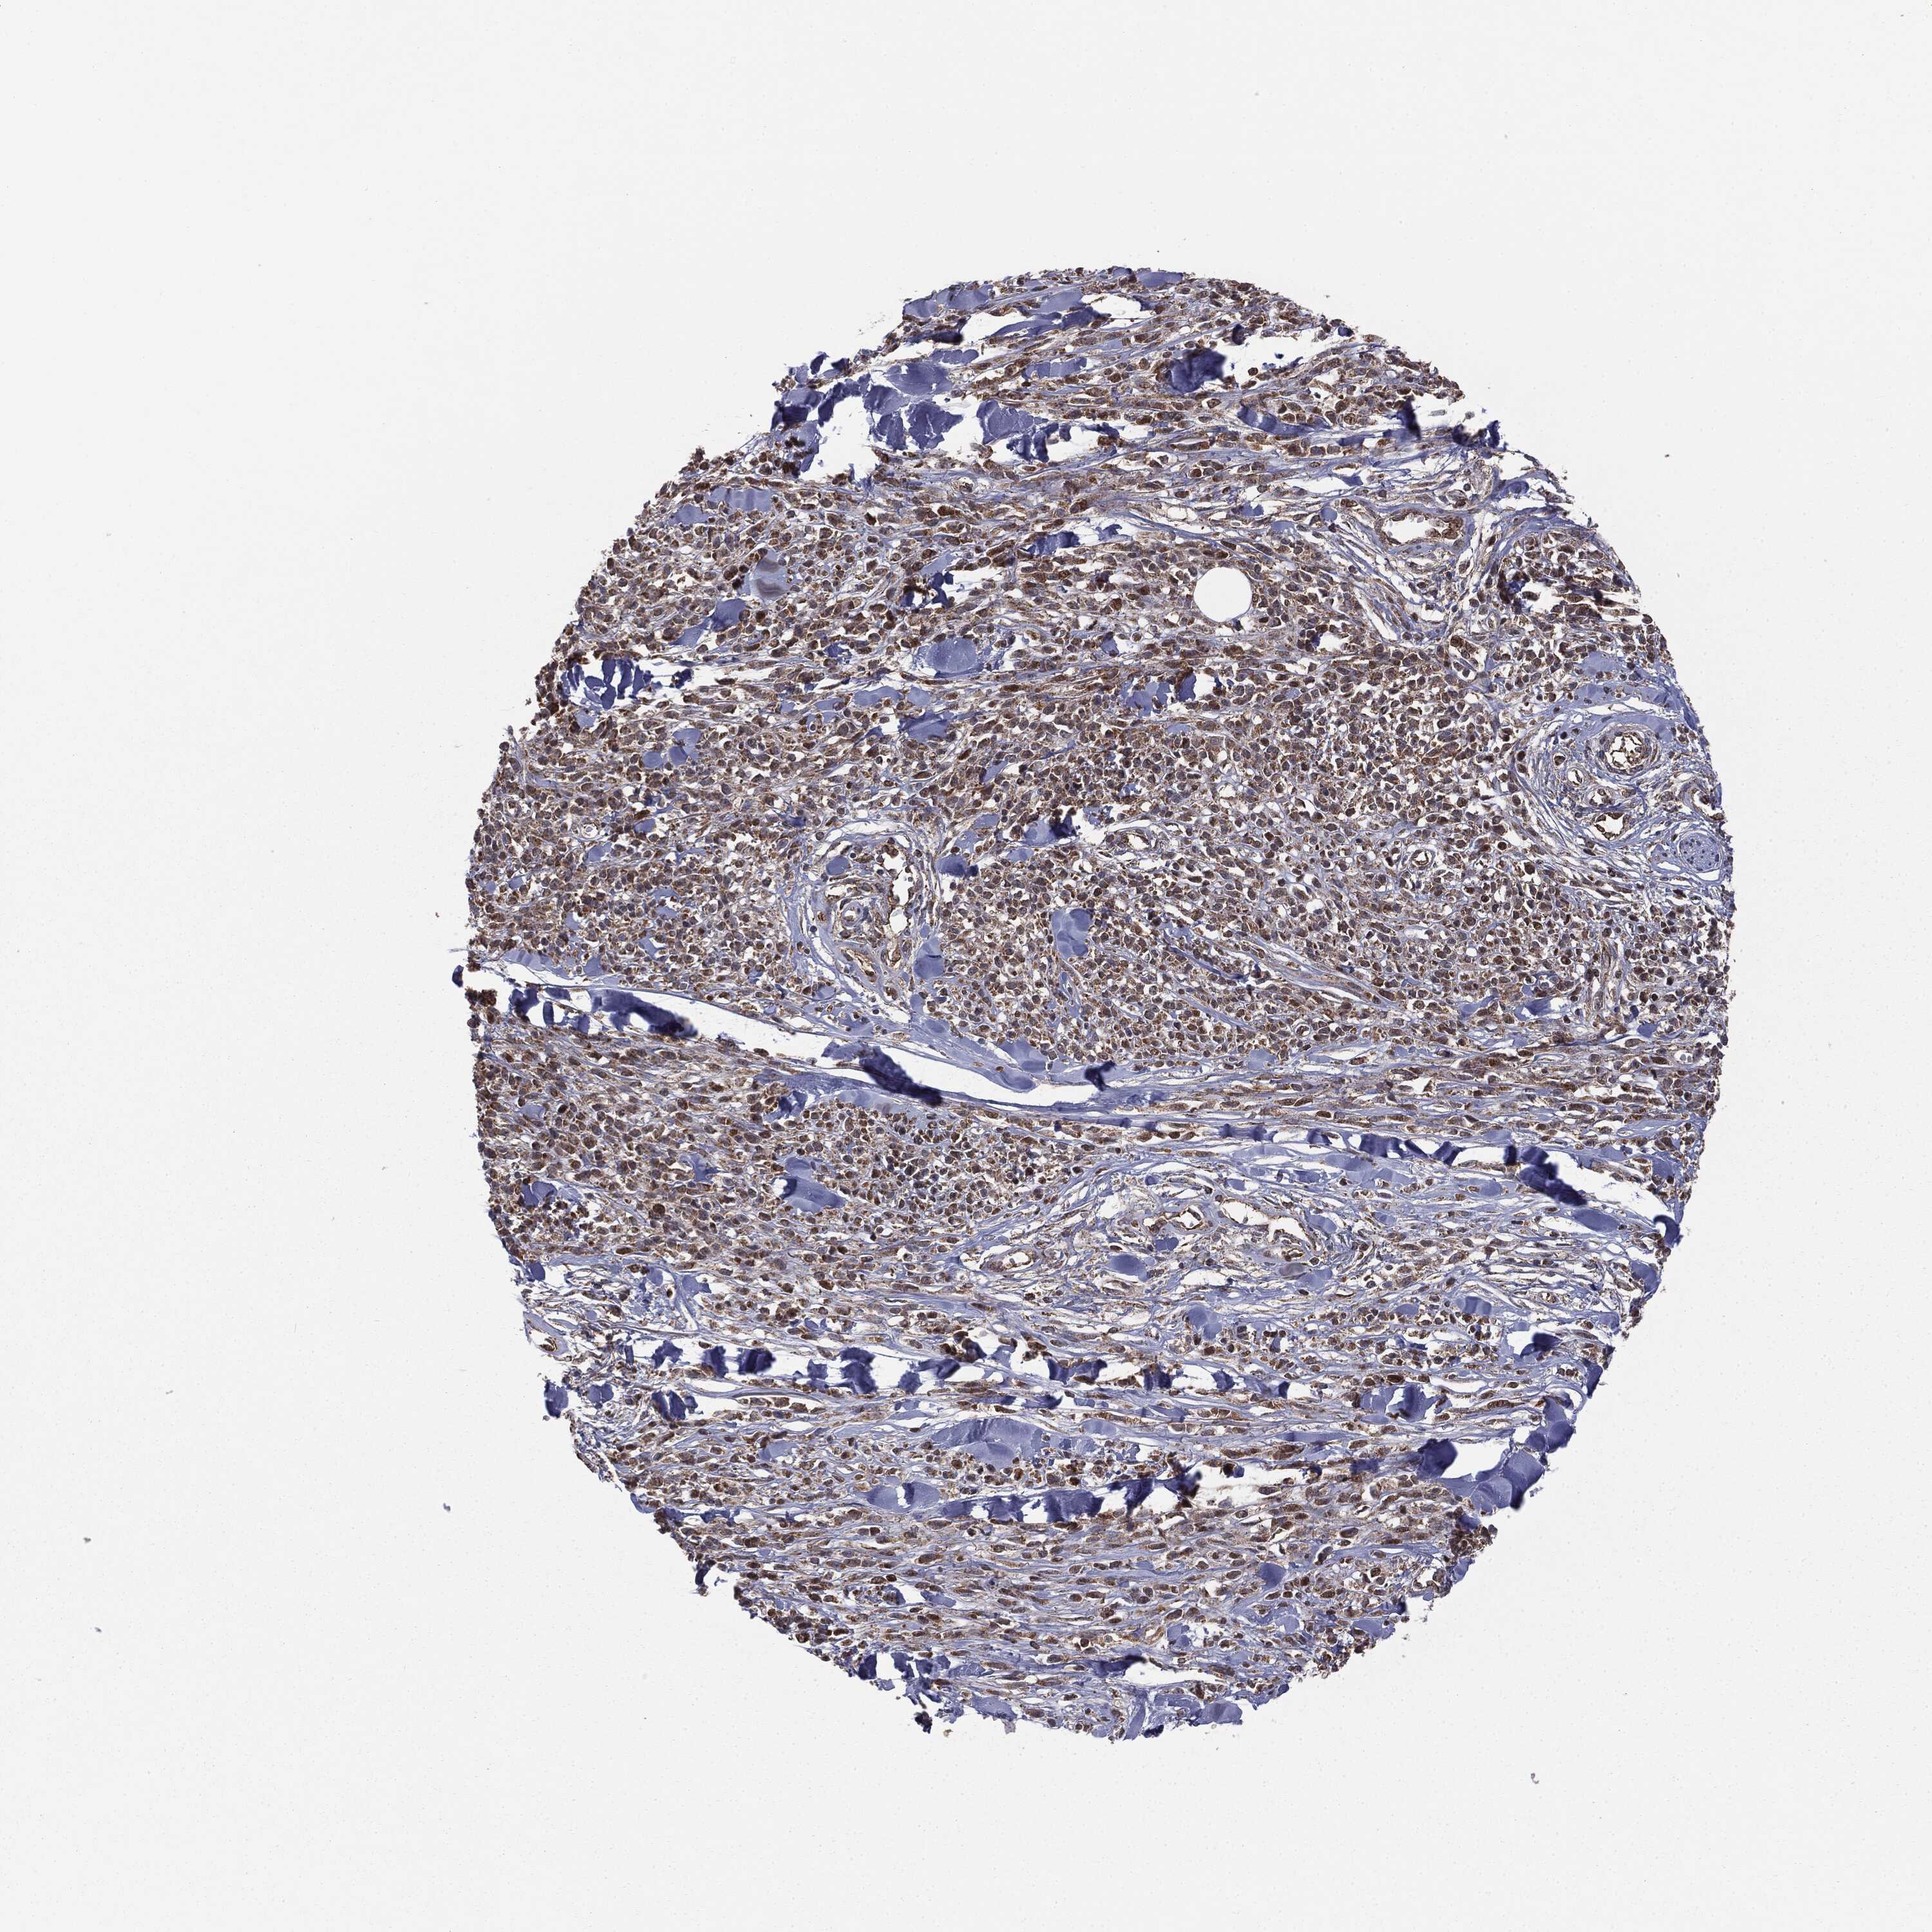

MELANOMA - Protein expressioni

A mouse-over function shows sample information and annotation data. Click on an image to view it in a full screen mode. Samples can be filtered based on level of antibody staining by selecting one or several of the following categories: high, medium, low and not detected. The assay and annotation is described here.

Note that samples used for immunohistochemistry by the Human Protein Atlas do not correspond to samples in the TCGA dataset.

Antibody stainingi

Antibody staining in the annotated cell types in the current human tissue is reported as not detected, low, medium, or high, based on conventional immunohistochemistry profiling in selected tissues. This score is based on the combination of the staining intensity and fraction of stained cells.

Each image is clickable and will lead to virtual microscopy that enables deeper exploration of all samples and also displays staining intensity scores, fraction scores and subcellular localization as well as patient and tissue information for each sample.

Malignant melanoma, NOS

Malignant melanoma, Metastatic site